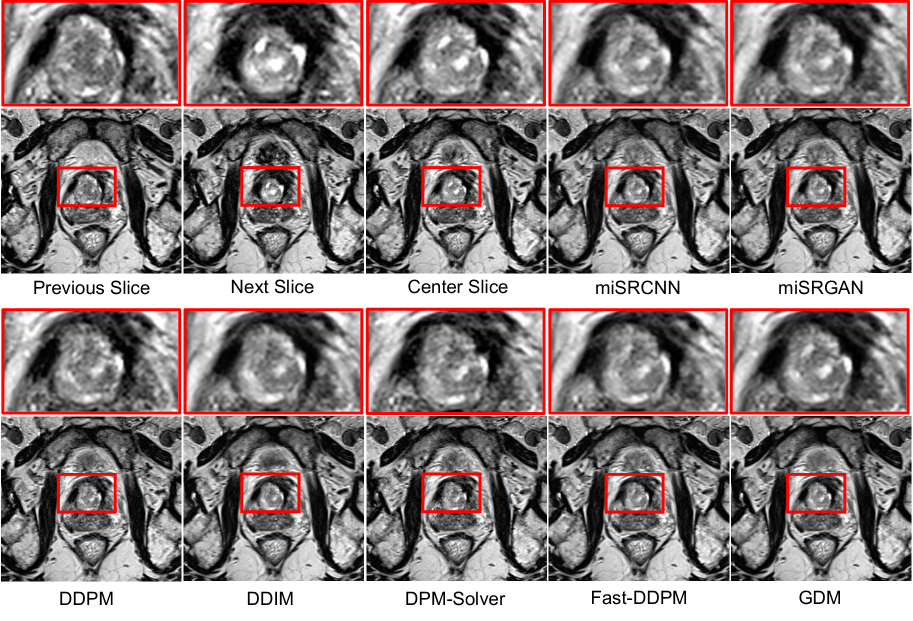

For MRI super-resolution, we compared GDM against a convolution-based model (miSRCNN [5]), a GAN-based model (miSRGAN [30]), and the same four diffusion-based baselines as in CT denoising. As shown in Table 1, GDM achieves state-of-the-art performance, surpassing all baselines. Even without truncated sampling, GDM ranks second overall, consistently outperforming prior methods. This demonstrates the effectiveness of geodesic trajectories in recovering subtle anatomical structures while suppressing noise. Beyond accuracy, GDM also delivers substantial efficiency gains, reducing training time by more than 20×20\times compared to DDPM and 4×4\times compared to Fast-DDPM, while pushing inference speed closer to that of lightweight regression-based models. This dual advantage underscores GDM’s potential as a practical solution for real-world MRI super-resolution, where both accuracy and scalability are critical.

Refer to caption

Figure 5: Qualitative results of MRI image super-resolution. While CNN- (miSRCNN) and GAN-based (miSRGAN) methods produce blurry outputs and other diffusion models lose fine details, our proposed GDM reconstructs sharper anatomical structures and closely matches the ground-truth center slice.

Figure 5 provides qualitative comparisons on prostate MRI, where the center slice is reconstructed from adjacent slices. CNN-based models such as miSRCNN yield over-smoothed predictions, achieving higher PSNR but lower SSIM. Diffusion-based models preserve more detail, yet most fail to recover the bright regions in the upper-left corner. In contrast, GDM reconstructs these regions with sharp structural fidelity, closely matching the ground truth and demonstrating robustness in handling challenging anatomical variations.